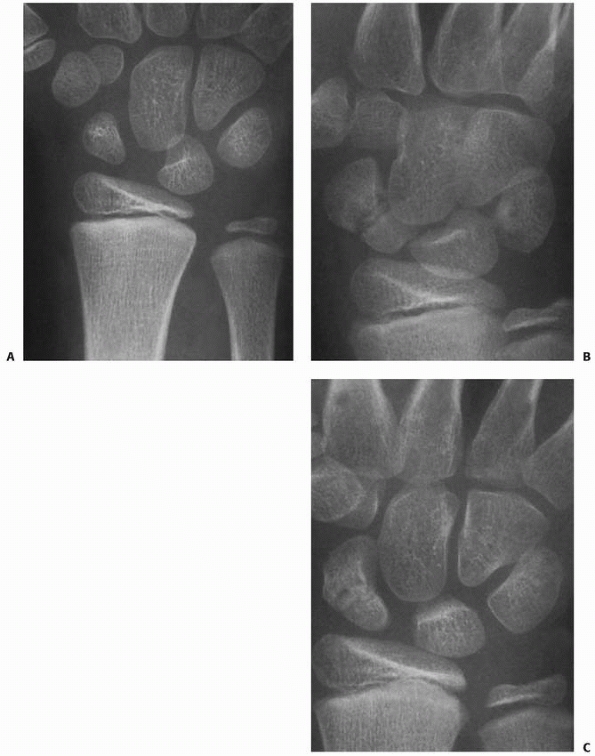

views are mandatory. Oblique radiographs are often helpful to determine

fracture configuration and alignment. Failure to recognize the extent

of injury is an ongoing problem, especially with unicondylar and

bicondylar fractures. These fractures may appear fairly normal on the

anteroposterior view, but a slight overlap of the subchondral surfaces

usually is present on the true lateral projection. This “double

density” shadow is made by the offset of the displaced condyle and

should not be regarded as a normal finding (Fig. 8-28).

![]() |

|

FIGURE 8-28 A. Anteroposterior radiograph reveals intra-articular fracture of the small finger. B. Lateral view demonstrates double density sign indicative of displacement (arrows).